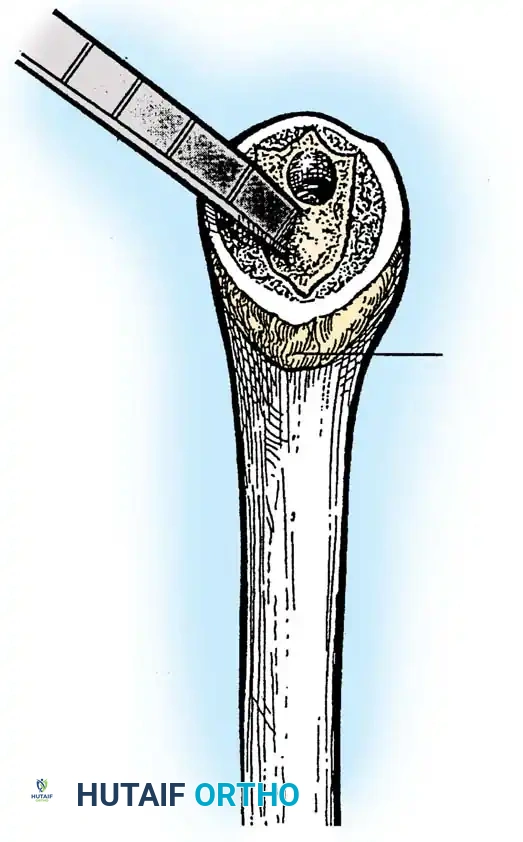

3. Humeral Head Resection

Dislocate the humeral head anteriorly through external rotation and extension. Remove peripheral osteophytes to identify the true anatomical neck. The humeral cut is made along the anatomical neck, typically at 30 degrees of retroversion and 45 degrees of inclination.